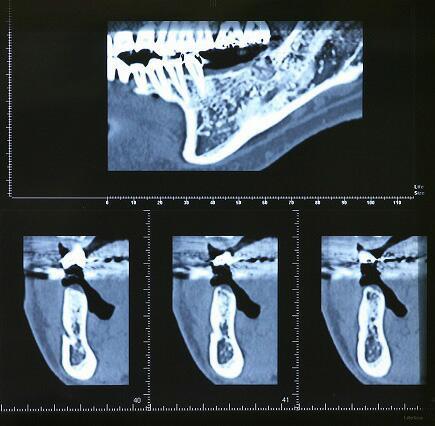

抜歯4ヶ月後のCTエックス線

輪切りにされた下顎骨

・真上の写真の楔状の切れ目はオトガイ神経の出口でインプラント埋入手術時は避けなければならない場所です

・このCTレントゲンによってインプラント埋入手術の安全性が大変高まっています

・このCTレントゲンを検討し、インプラント体(フィクスチャー)埋入場所、太さ等を決めていきます